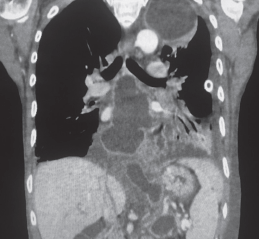

Casos Clínicos

Manuel Quiroz F., Minerva Jara C., Manuel Novajas B.

|

Osvaldo Valdés Dupeyrón

Rodrigo Hernández Negrin, Mauricio Pontillo, Eduardo Olivera, Gustavo Rodríguez

Francisco Ortega Gonzalez, Nicolas Yañez Benavides, Cesar Muñoz Castro, Dahiana andrea Pulgar Boin